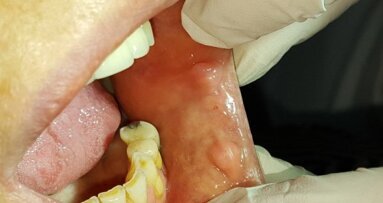

38-letni pacjent, ogólnie zdrowy, niepalący zgłosił się w celu uzupełnienia braku zęba 11. Mężczyzna został pobity, w wyniku czego doszło do złamania korony zęba 21 oraz złamania korony i korzenia zęba 11 (Ryc. 1).

Ze względu na inne obrażenia ciała zaplanowano ekstrakcję oraz wczesną implantację. Ząb 11 został usunięty, a zębodół zaopatrzono Biocollagenem (Ryc. 2). Ząb 21 odbudowano oraz opracowano pod uzupełnienie tymczasowe (Ryc. 3). Po 8 tygodniach przystąpiono do zabiegu implantologicznego. Po odpreparowaniu płata stwierdzono ubytek policzkowej blaszki kostnej (Ryc. 5). Przygotowano łoże implantu w obrębie okna estetycznego (Ryc. 6) i wprowadzono implant BEGO Semados S 4, 1L 13 (Ryc. 7 i 8). Wykonano augmentację biomateriałem BEGO Oss, który pokryto błoną kolagenową BEGO Membrane w technice dwuwarstwowej (Ryc. 9 i 10). Ranę zaszyto szwami nieresorbowalnymi.